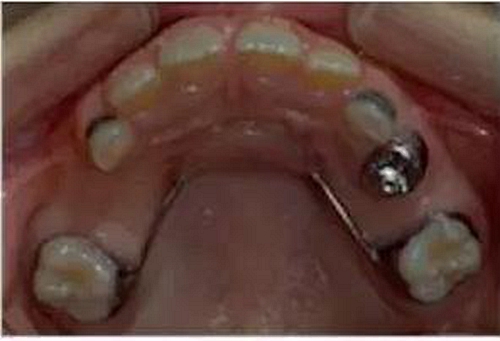

③Nance弓(腭弓)式間隙保持器

乳牙缺失致恒牙“亂長”,這個(gè)“間隙保持器”可預(yù)防

Nance弓式間隙保持器,也稱為腭弓式間隙保持器,是用于上牙需要間隙保持的部位,它和舌弓式間隙保持器是相對(duì)應(yīng)的。